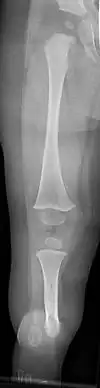

| a, b) Paley type 3c fibular hemimelia | |